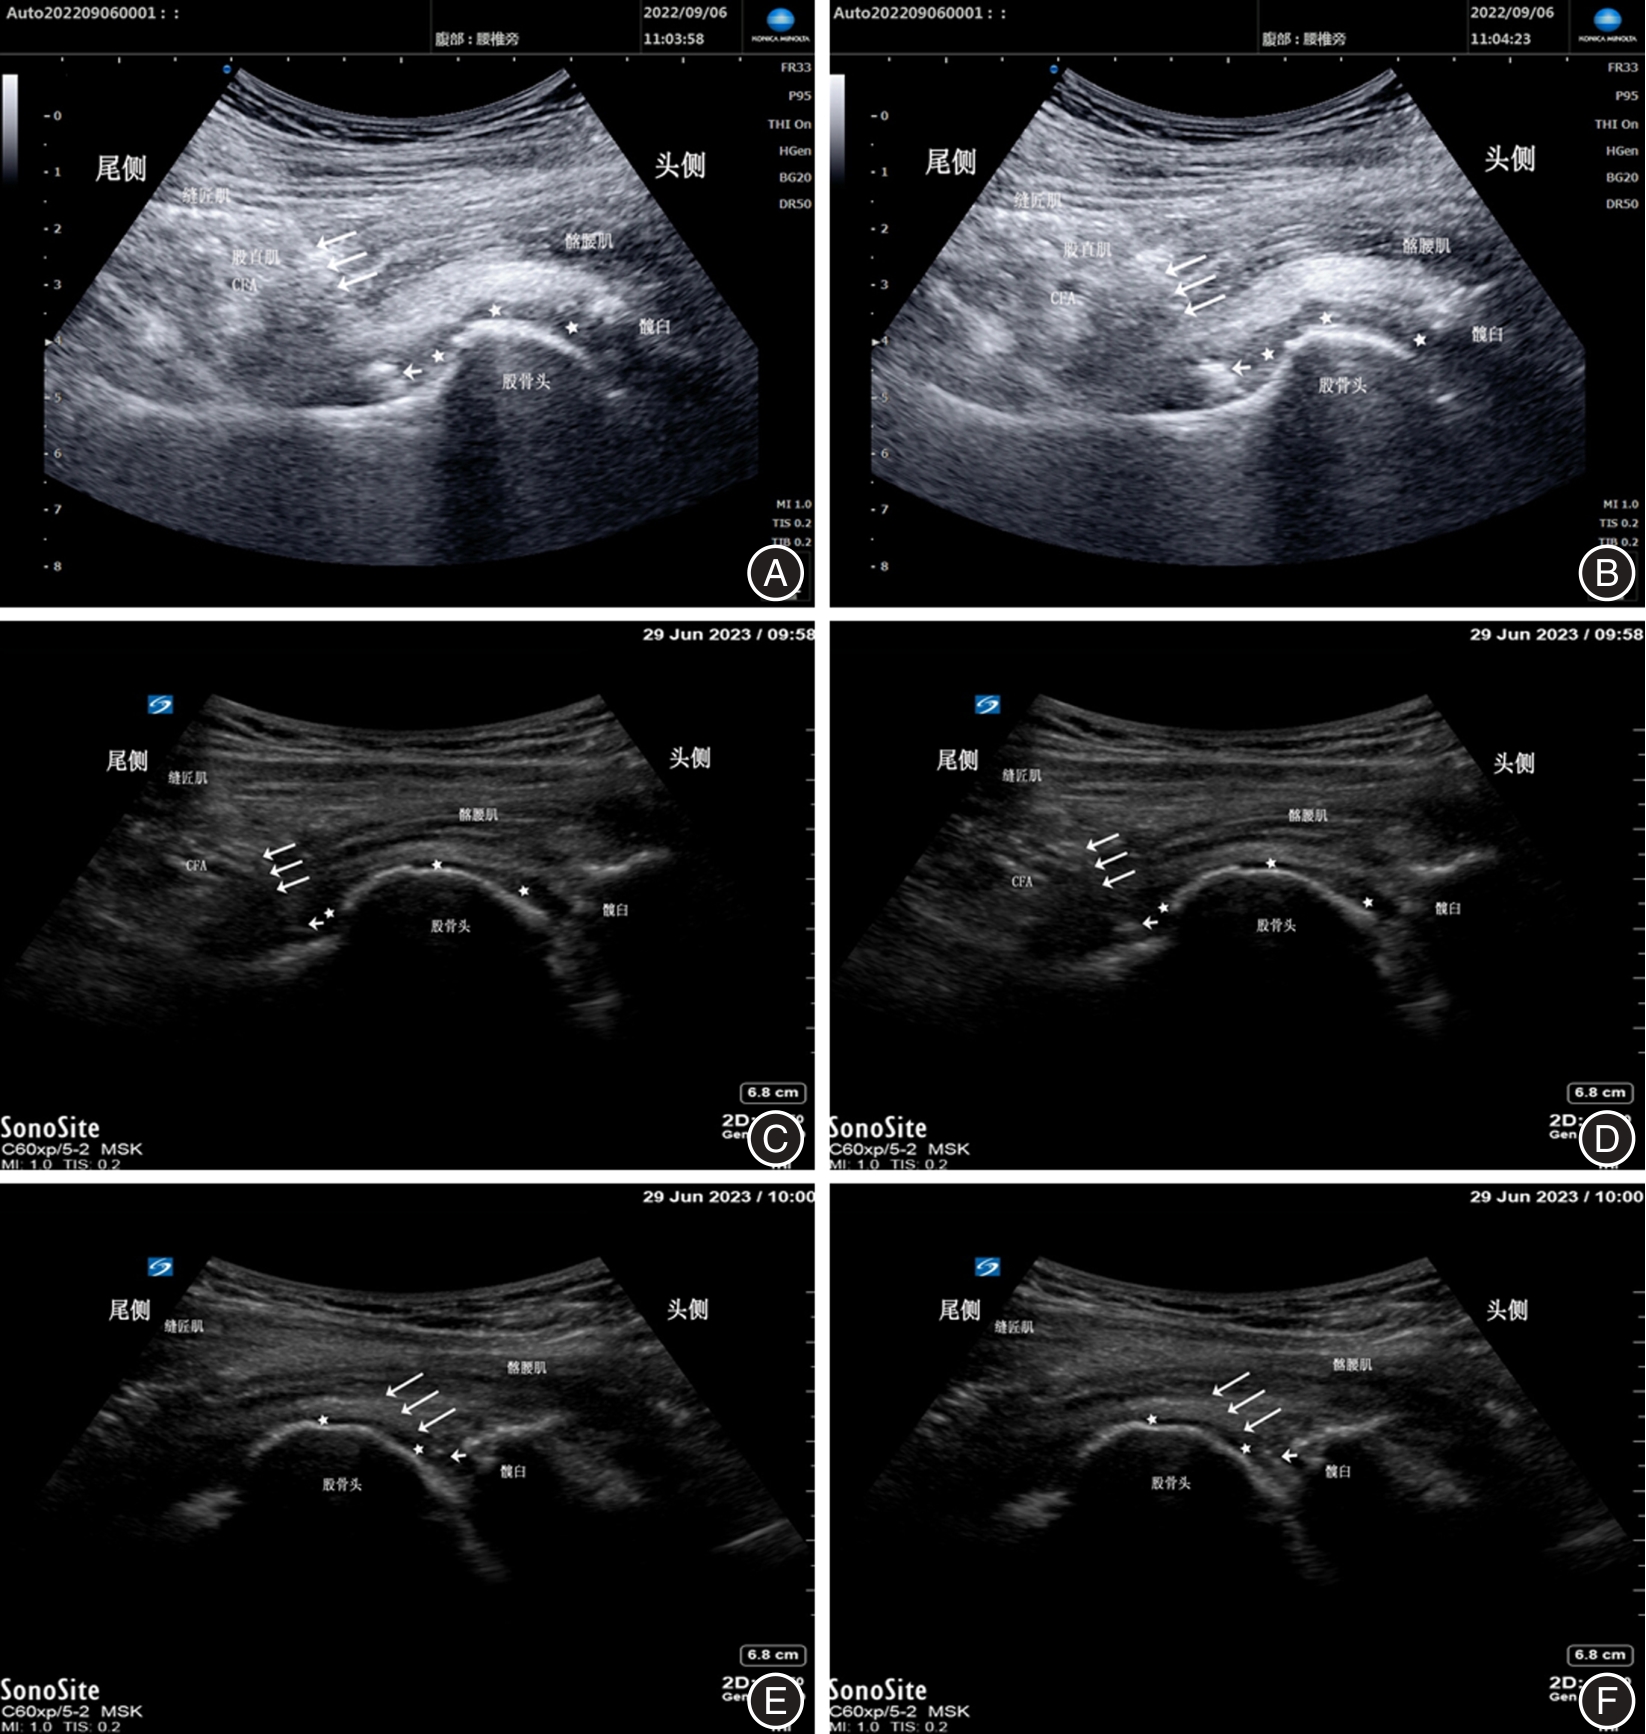

LYNCH T S, OSHLAG B L, BOTTIGLIERI T S, et al. Ultrasound-Guided Hip Injections[J]. J Am Acad Orthop Surg,2019,27(10):e451-e461. doi:10.5435/jaaos-d-17-00908

HOEBER S, ALY A R, ASHWORTH N, et al. Ultrasound-guided hip joint injections are more accurate than landmark-guided injections: A systematic review and meta-analysis[J]. Br J Sports Med,2016,50(7):392-396. doi:10.1136/bjsports-2014-094570

GAO G, FU Q, WU R, et al. Ultrasound and Ultrasound-Guided Hip Injection Have High Accuracy in the Diagnosis of Femoroacetabular Impingement With Atypical Symptoms[J]. Arthroscopy,2021,37(1):128-135. doi:10.1016/j.arthro.2020.08.013